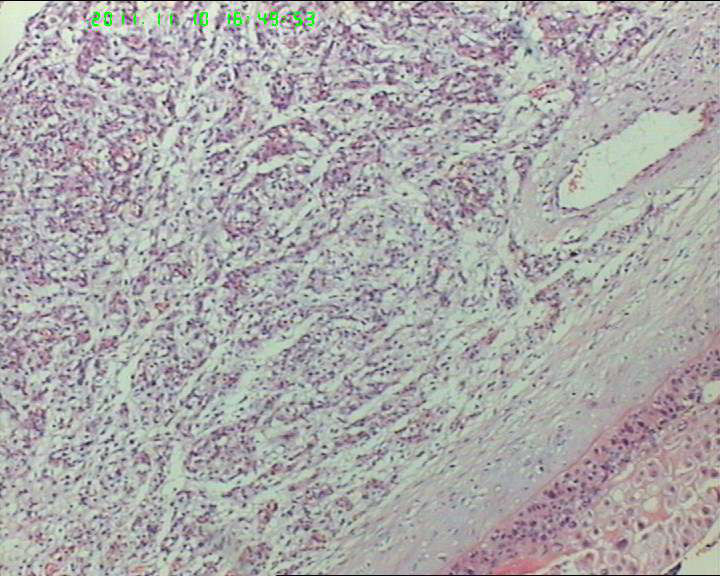

19岁,停经33周,前置胎盘,剖宫产。胎盘母体面可见一灰褐色结节,直径约5.5cm,包膜完整,切面实性,质略嫩。

典型的绒毛膜血管瘤

典型的胎盘毛细血管瘤,发病率约1%,前一阵刚遇到一例。

毛细血管瘤,胎盘常见的肿瘤